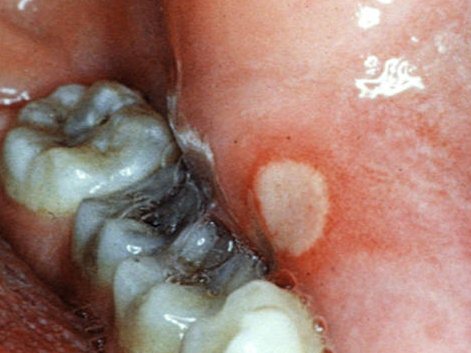

Афтозный стоматит – хроническое заболевание слизистой оболочки ротовой полости. Характеризуется появлением множественных либо единичных афт. Форма афт, как правило, круглая или овальная с характерными границами красной каймы и налетом серо-желтого цвета в центре афты.

Афта – небольшое изъязвление поверхности слизистой оболочки, чаще всего ротовой полости. Афты могут развиваться в виде самостоятельного заболевания (у детей) либо как осложнение другого острого желудочно-кишечного или инфекционного заболевания (гриппа, ящура и т.д.)

Афтозный стоматит, как правило, сопровождается болезненной отечностью слизистой оболочки ротовой полости, которая покрывается налетом желтоватого или белого цвета. Отмечается повышенное слюноотделение (гиперсаливация), неприятный запах изо рта и, в некоторых случаях, кровоточивость десен.